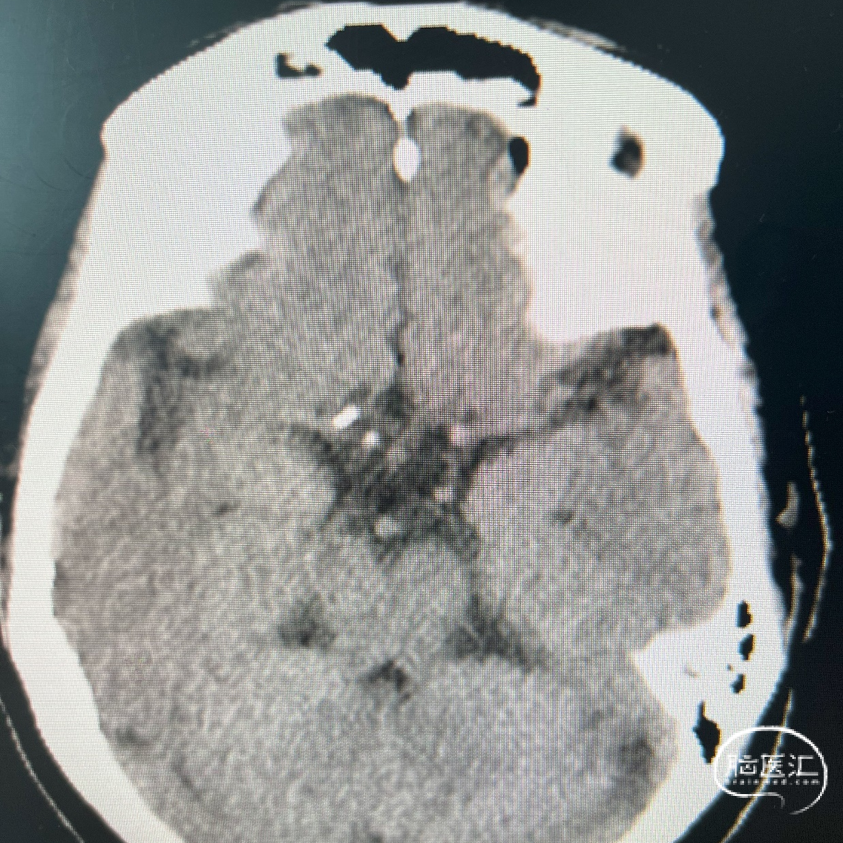

术前影像资料

术前辅助检查:

影像学表现:

1、主动脉弓及其他弓上血管,III型弓,弓上血管迂曲,血管通畅。

2、颈内动脉系统:

右侧颈总动脉及颈内动脉血管通畅,远端右侧大脑中动脉血流通畅,可见同侧及对侧大脑前动脉显影。

左侧颈总动脉及颈内动脉血流通畅,后交通开放,可见同侧大脑后动脉显影,大脑前动脉血流通畅。

3、椎基底动脉系统:

右侧椎动脉优势型。

左侧椎动脉血管纤细,远端可见基底动脉浅淡显影。

右侧椎动脉优势型,远端汇入基底动脉。

基底动脉中段重度狭窄,狭窄率约80%,双侧大脑后动脉可见显影。